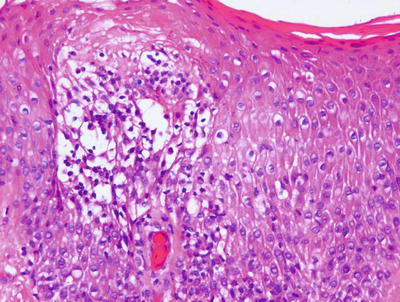

Allergic contact dermatitis is a spongiotic process, characterized by parakeratosis (except in the acute state), marked intraepidermal edema and abundant Langerhans cell microabscesses [45] (Fig. 1.13). In florid cases, the spongiosis results in microvesiculation. Eosinophils are abundant within the dermis and may extend into the epidermis (Fig. 1.14). A brisk lymphohistiocytic inflammatory infiltrate is present surrounding vessels of the superficial vascular plexus. Ordinarily, the inflammation does not extend into the lower portions of the dermis [46, 47].

Fig. 1.14

Allergic contact dermatitis frequently displays spongiotic microvesicles that contain eosinophils. Abundant eosinophils are characteristic of this disease